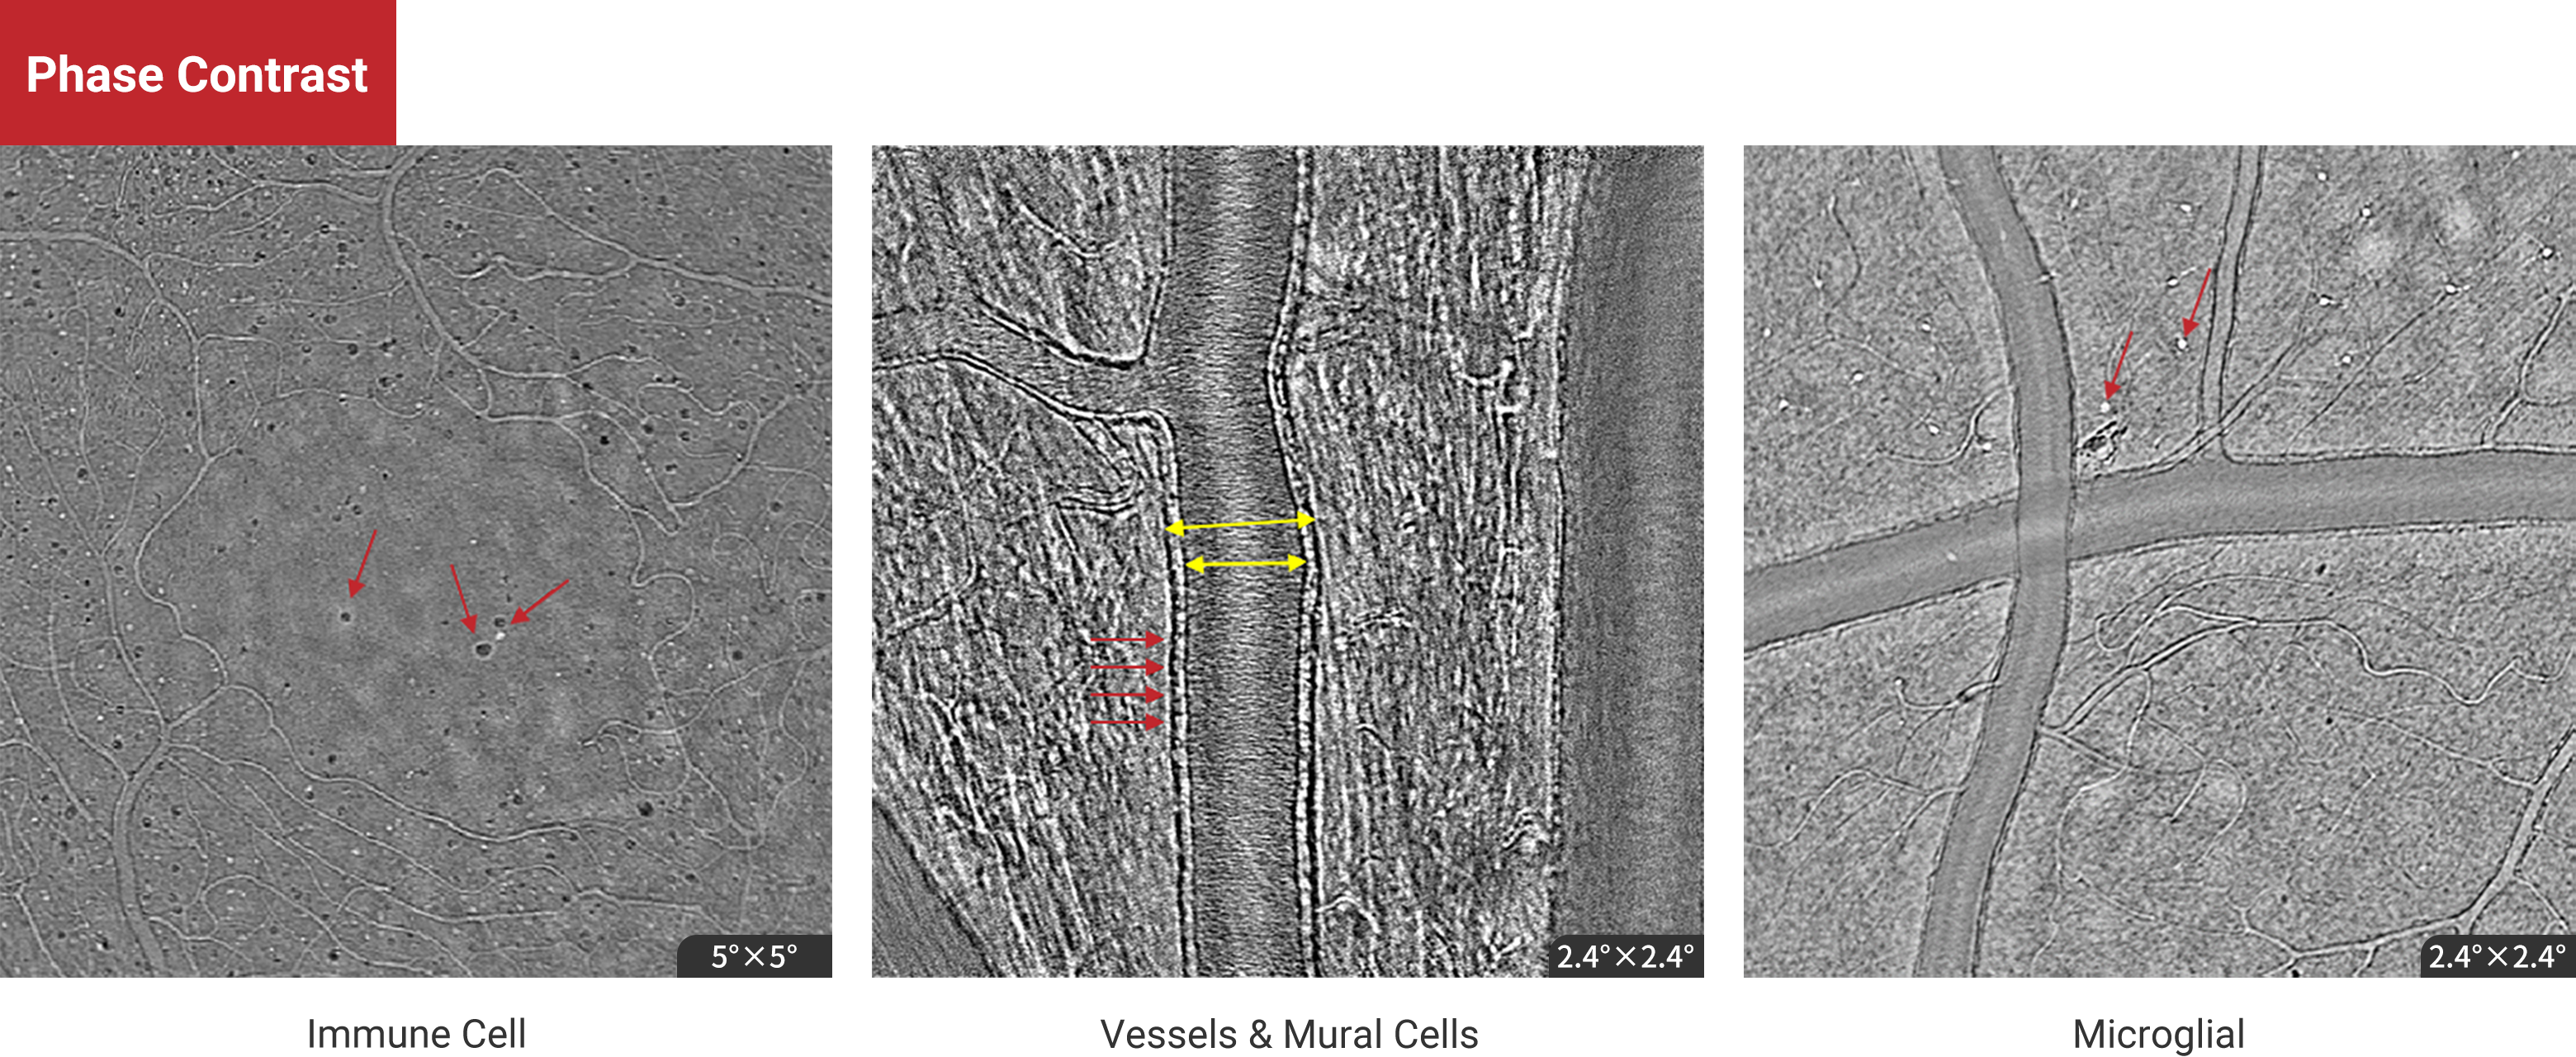

Phase Contrast